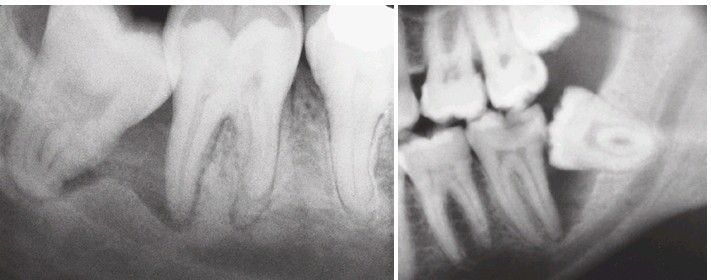

Impacted 3rd molars

Radiographs showing variations of a mandibular third molar impacted against a second molar with severe bone loss resulting from periodontal disease and a third molar.